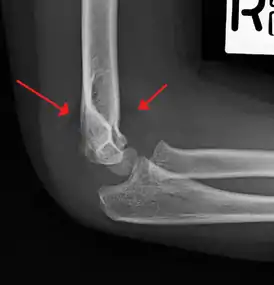

| An elbow X-ray showing a displaced supracondylar fracture in a young child | |

X-rays

Diagnosis is confirmed by x-ray imaging. Antero-posterior (AP) and lateral view of the elbow joint should be obtained. Any other sites of pain, deformity, or tenderness should warrant an X-ray for that area too. X-ray of the forearm (AP and lateral) should also be obtained for because of the common association of supracondylar fractures with the fractures of the forearm. Ideally, splintage should be used to immobilise the elbow at 20 to 30 degrees flexion in order to prevent further injury of the blood vessels and nerves while doing X-rays. Splinting of fracture site with full flexion or extension of the elbow is not recommended as it can stretch the blood vessels and nerves over the bone fragments or can cause impingement of these structures into the fracture site.[2]

Depending on the child's age, parts of the bone will still be developing and if not yet calcified, will not show up on the X-rays. The capitulum of the humerus is the first to ossify at the age of one year. Head of radius and medial epicondyle of the humerus starts to ossify at 4 to 5 years of age, followed by trochlea of humerus and olecranon of the ulna at 8 to 9 years of age, and lateral epicondyle of the humerus to ossify at 10 years of age.[2]